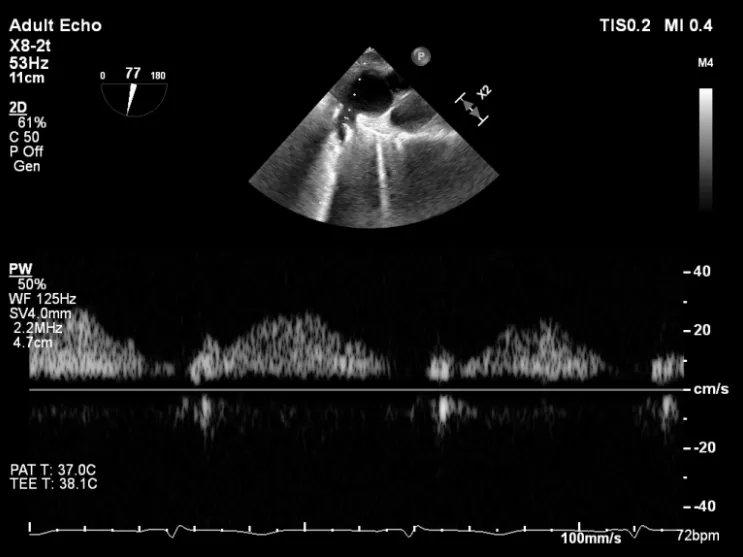

第二枚XTR植入后瓣口平均压差3mmHg

第3枚XTR夹合器植入后,跨瓣平均压差为3mmHg

夹子释放Bi-com切面显示残余反流情况

术后2D TTE:

术后TTE可见二尖瓣微量-轻度反流,三尖瓣反流明显改善降至中度